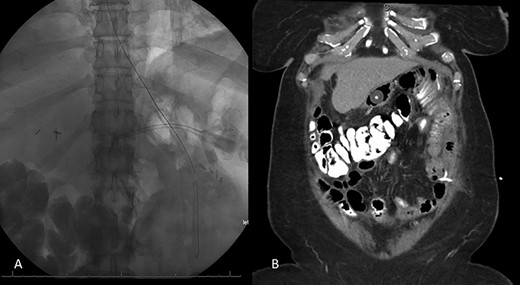

Decision was made to explore and attempt to excise the infarcted omentum. She was taken to the operating room and underwent a diagnostic laparoscopy. However, due to the large size of the omental infarction with an encapsulated necrotic liquefied, purulent secretion and significant adhesions, we decided to convert it to a midline laparotomy. We then proceeded with resection of right-sided infarcted, necrotic, liquefied omentum and abdominal washout (Fig. 3). Culture from the purulent secretion that was inside encapsulated omentum grew Streptococcus anginosus. She received Meropenem and Fluconazole. She had a prolonged and protracted recovery with a transient kidney injury and the development of multiple intra-abdominal (inter-loop, peri-hepatic, peri-splenic and pelvic) fluid collections (Fig. 4A). These collections were treated by percutaneous drainage (pelvis × 1, perisplenic and left-sided collections × 2). Three weeks from the take back, she developed a small bowel obstruction with significant dilation of the biliopancreatic limb and excluded stomach (Fig. 4B and C). She was taken to the operating room and had an endoscopically placed nasogastric tube just passed the jejunojejunostomy. Then, she underwent CT-guided gastrostomy tube to decompress in the gastric remnant (Fig. 5 A and B). One week after the rendezvous nasogastric and gastric remnant decompression, an oral and through the G-tube contrast study demonstrated patency of the gastrojejunostomy and resolution of the small bowel obstruction (Fig. 6). The patient was discharged home on POD #39 tolerating a regular postbariatric surgery diet.

A: Abdominal and pelvic CT scan obtained at POD # 29. From index RYGB and POD # 8 from excision of infarcted omentum showing loculated perisplenic, pelvic and perihepatic fluid collections. B and C: Abdominal and pelvic CT scan obtained at POD # 20 from take back and plain X-ray showing gaseous distention of the excluded stomach and duodenum, confirming a small bowel obstruction of the biliopancreatic limb.